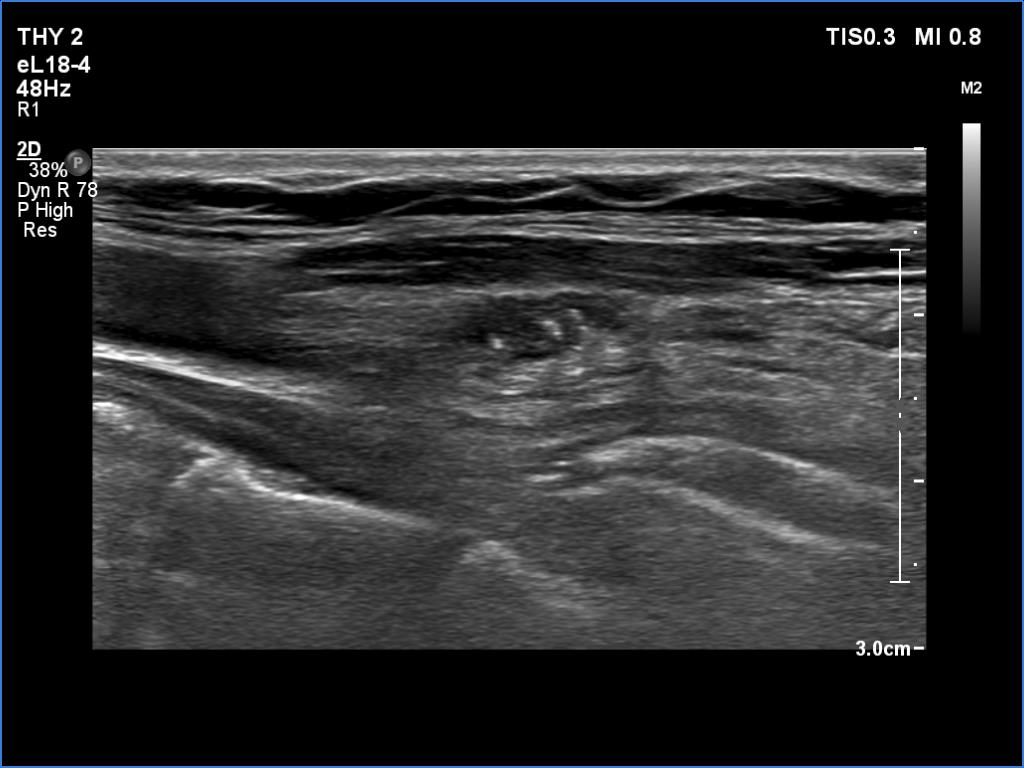

Ultrasonography. The right lobe was replaced with connective tissue. A hypoechoic mass was found in the left thyroid bed. On certain sections, this mass was very similar to a muscle fiber, however some other sections proved the presence of intralesional echogenic figures; the presence of back wall cystic figures was obvious but in the event of some granules microcalcifications should be considered. The lesion was vascularized, which excluded that the mass is muscle fiber.